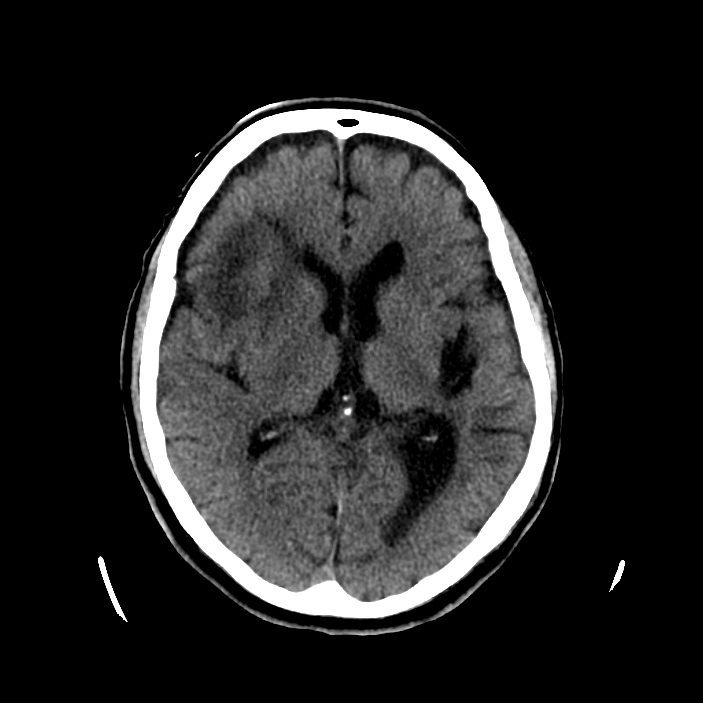

Se realiza un TC de cráneo sin contraste, estos son los hallazgos:

Esta imágen plantea dudas, puede ser una masa o un foco de sangrado, es más, si de esta segunda imagen asumimos que la zona de densidad aumentada corresponde a un sangrado, la pregunta a realizarse ahora es ¿de qué tipo? ¿Es un sangrado intraparenquimatoso, una transformación hemorrágica de un infarto o es otra cosa?